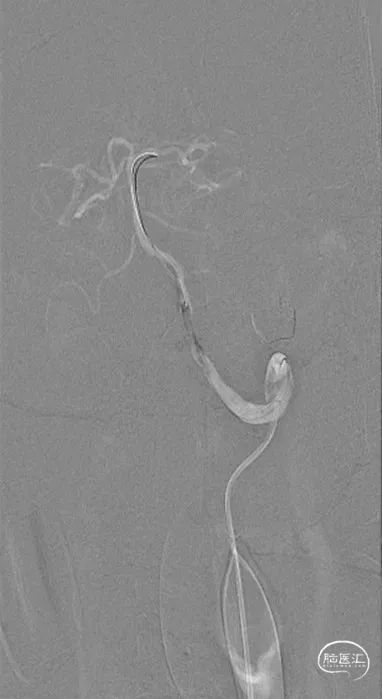

外院DSA(2023.02.09):左侧椎动脉V4段重度狭窄,右侧椎动脉V3段远端闭塞。前循环未见明显异常。

置鞘成功

鞘内造影

锁骨下造影

近椎口造影